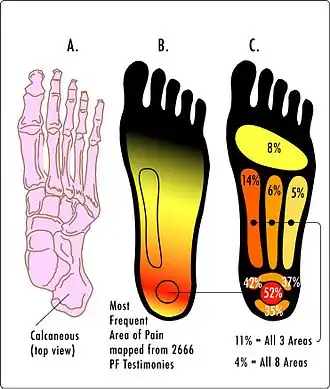

Локализация болевых ощущений при плантарном фасциите | |

Подошвенный фасциит является наиболее распространенной причиной боли в пятке, которая особенно сильно ощущается в начале ходьбы (утром при первых шагах). Кроме того, при подошвенном фасциите может болеть свод стопы и лодыжка.

Характеризуется появлением боли в месте прикрепления подошвенной фасции к пяточной кости (пяточная энтезопатия), которая может иррадиировать вдоль медиального края подошвенной фасции. Диагностика основывается на клинических данных.

Ведущий симптом плантарного фасциита — боли в пяточной области, возникающие или усиливающиеся при нагрузке. Болевые ощущения более выражены в утренние часы. В большинстве случаев для диагностики плантарного фасциита достаточно анализа жалоб пациента, физикального осмотра и рентгенографии, позволяющих выявить наличие пяточной шпоры. Отсутствие пяточной шпоры в совокупности с пяточной болью требуют дифференциального диагноза, в первую очередь, с системными воспалительными заболеваниями (ревматоидный артрит, синдром Рейтера и др.), которые также могут дебютировать пяточной болью. Фасциит может осложняться переломами остеофитов.